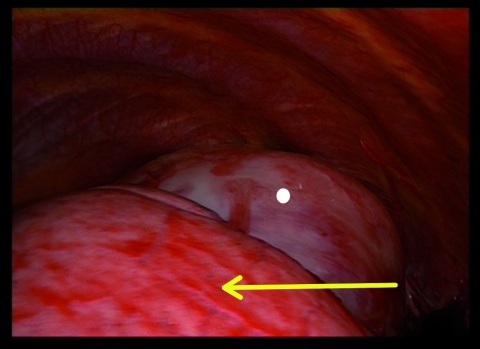

Zwei Tage nach Aufnahme zeigte der Patient einen starken Hämoglobinabfall von 12,4 g/dl auf 7,9 g/dl, so dass eine notfallmäßige Thorakoskopie zur Blutstillung und Histologiegewinnung durchgeführt werden musste. Auf eine erneute Bildgebung präoperativ wurde hierbei aufgrund eines symptomatischen Patienten mit Kurzatmigkeit und niedrigem Hämoglobinwert verzichtet. Bei dem Eingriff bestätigte sich der initiale Verdacht eines Hämatothorax. Es konnten 1,5 l teils frischen, teils mit Koageln durchsetzten Blutes abgesaugt werden. Es zeigte sich links apikal ein von der dorsalen Thoraxwand ausgehender und dort adhärenter Tumor mit erkennbarem Tumorstiel, von welchem die Blutung ausging. Aufgrund der thorakoskopisch schlechten Zugänglichkeit der Blutung und der Kontaktfläche zur Thoraxwand wurde eine Thorakotomie durchgeführt, die Blutung gestillt und der Tumor in toto entfernt.

Operative Therapie

Bei der Thorakoskopie zeigte sich die Lunge makroskopisch unauffällig und nur durch kleinere Adhäsionen im Bereich des Oberlappens mit dem Tumor verbunden. Der Tumor selbst war solide, von einer Kapsel umgeben, bindegewebig und apikal dorsal an der Thoraxwand adhärent. Hinter dem Tumor bestand weiterhin eine Blutung, die thorakoskopisch nicht erreicht werden konnte; daher erfolgte der Entschluss zur Thorakotomie. Ob er ursprünglich von der Lunge oder der Thoraxwand ausging, ließ sich intraoperativ nicht mit letzter Sicherheit klären.